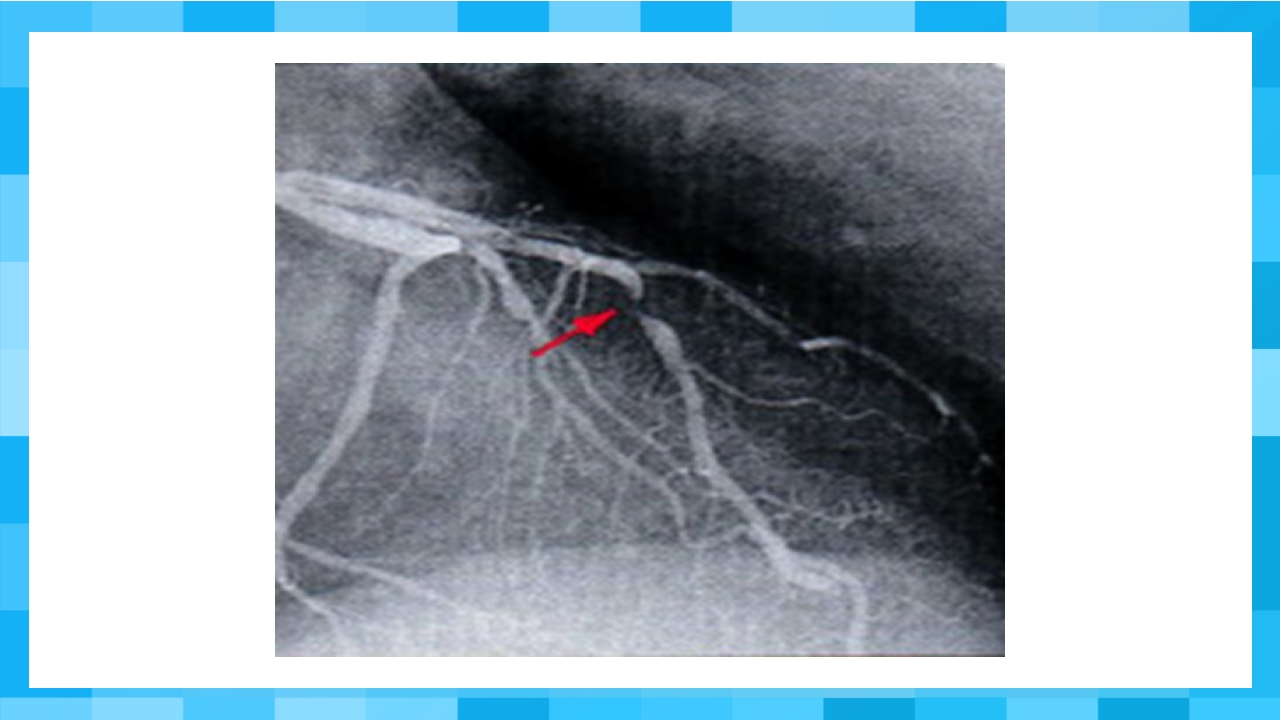

医-学-教-育-医-疗-健--康-宣-传 202X 急性冠脉综合征(ACS) 汇报人:xxx 汇报时间:20XX ACS的概念 ACS在冠状动脉粥样硬化病变 的基础上,病变斑块不稳定, 继而斑块破裂,引起不完全或 完全性堵塞性血栓急性病变, 导致冠状动脉内血流量减少的 一系列病理生理过程的临床综 合征。 NSTEMI 不稳定型心绞痛 NQMI QwMI 心肌梗塞 ST段持续抬高 血管完 全闭塞 (红色) 非ST段持续抬高 血管未完 全闭塞 (白色) ST段抬高心梗 死亡/猝死 CK-MB或肌钙蛋白升高 不稳定心绞痛,非ST段抬高心梗 进展为ST段抬高心梗 肌钙蛋白升高或正常 4 动脉粥样硬化斑块形成 内皮细胞 纤维帽 脂核 内膜平滑肌细胞 (修复型) 外膜 中层平滑肌细胞(收缩型) 5 不稳定性动脉粥样硬化斑块 外膜 斑块破裂、...